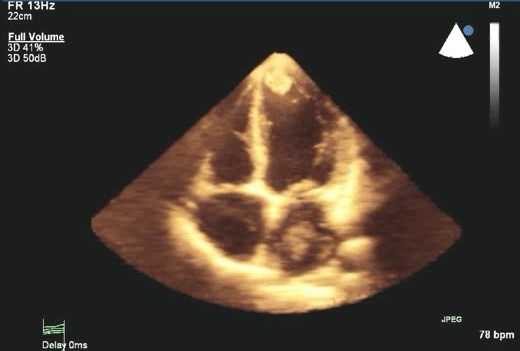

ЭхоКГ может определять местоположение, размер, подвижность, количество и прикрепление опухолей. Это особенно полезно при планировании хирургического лечения.

ЭхоКГ не позволяет отличить доброкачественные опухоли от злокачественных. 2-D эхокардиография показывает опухоли как эхогенные образования в полости сердца, прикрепленные к стенке или находящиеся в перикарде. Обычно их размер и мобильность можно хорошо определить. Как и во всех исследованиях при проведении ЭхоКГ, необходимо получить несколько изображений. Иногда в M-режиме можно увидеть опухоль, такую как миксома, нарушающая функцию клапана. Эффекты опухолей (например, обструкция клапана, дисфункция ЛЖ из-за инфильтрации, обструкции или перикардиального выпота) также можно увидеть на эхокардиографии.

Миксомы могут быть легко обнаружены с помощью M-режима или 2-D эхокардиографии. Миксома может рассматриваться как образование в полости ЛП и может пролабировать через МК в полость ЛЖ во время диастолы, затрудняя кровоток. Она может быть настолько большой, что заполняет все предсердие. Допплер может показать гемодинамические эффекты данной опухоли.